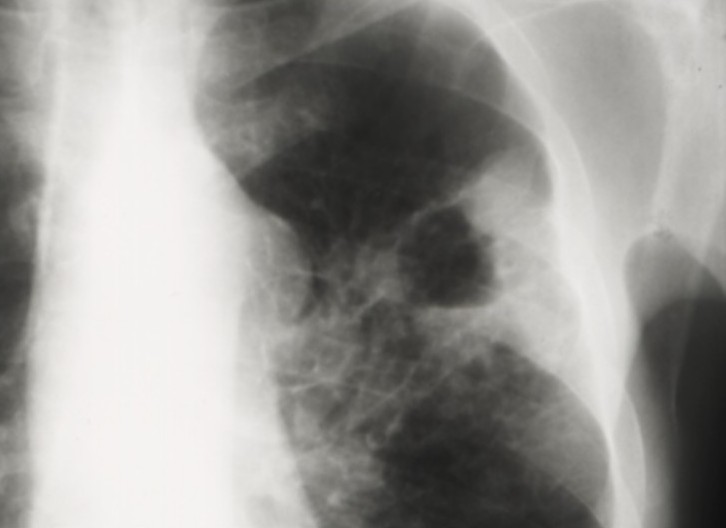

Cancers bronchiques